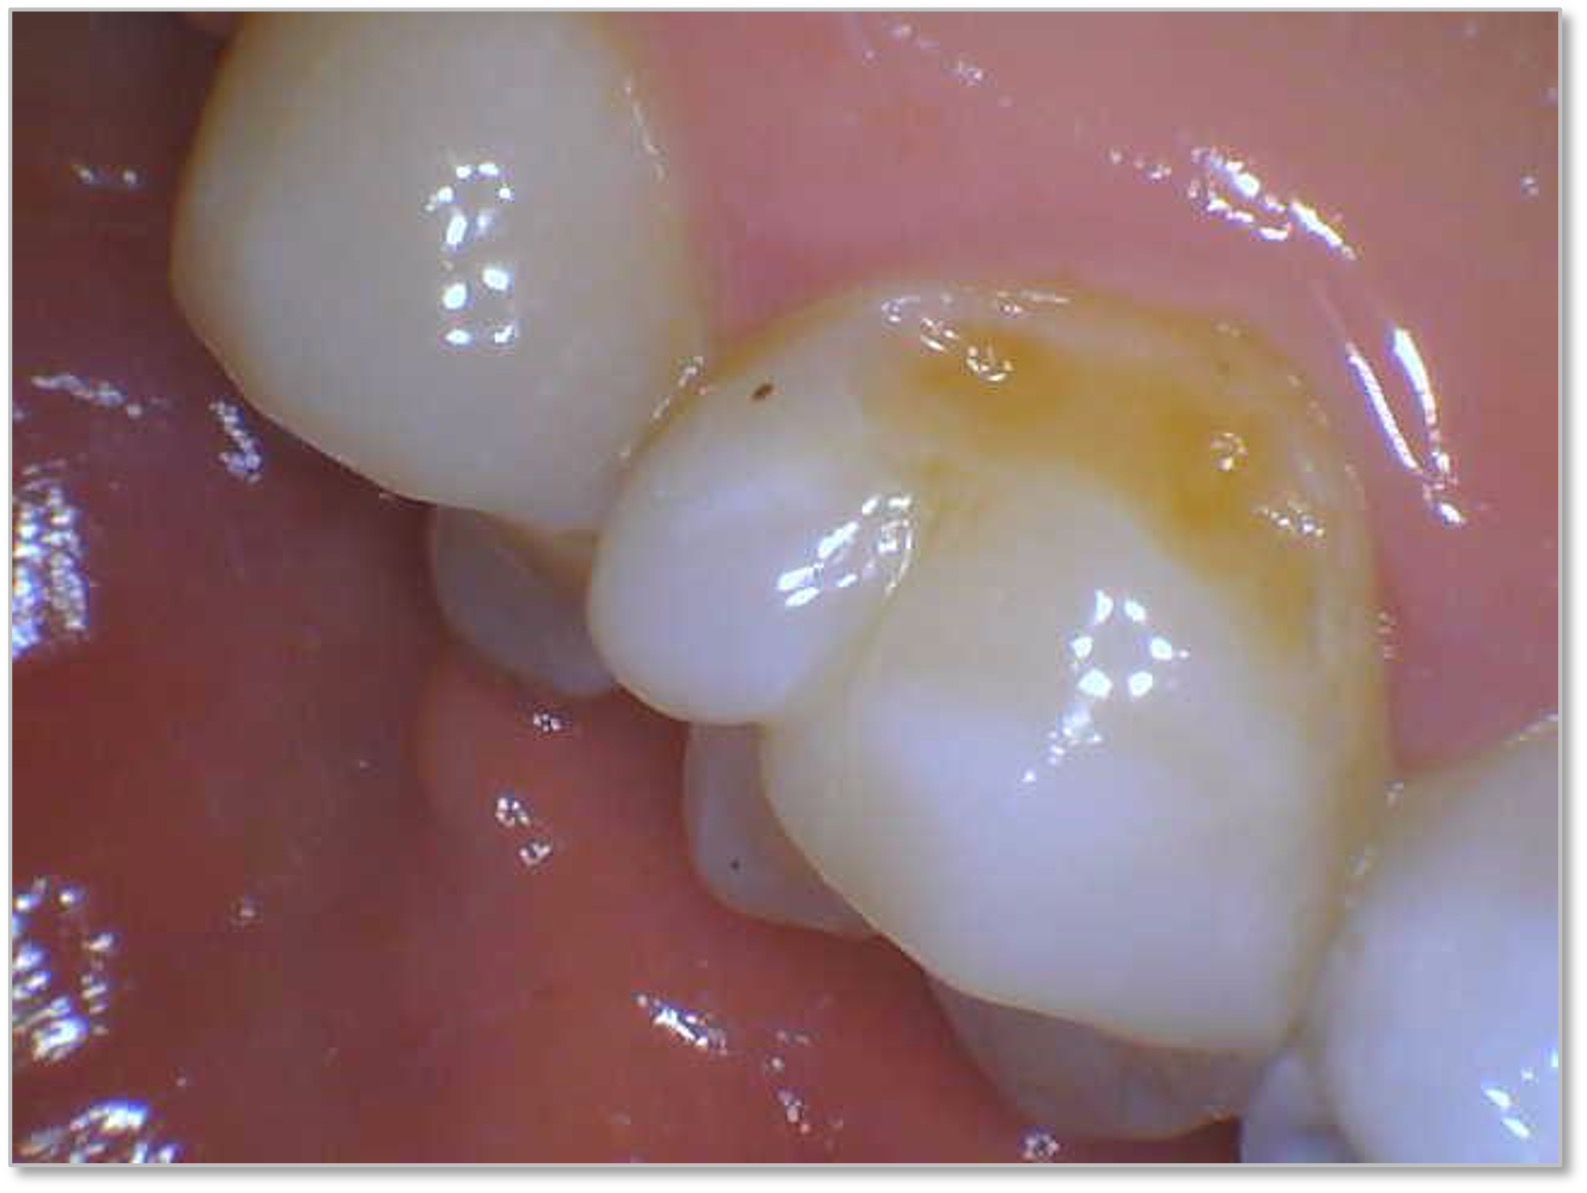

Figure 8a and Figure 8b show a terminal abutment with proximal decay from a removable cast metal partial denture. The tooth had an existing large resin restoration that was otherwise stable and the decay was isolated to the mesial surface. The patient had limited funds, and while a crown was presented as a restorative option, the patient elected to restore the tooth with a direct restoration at the time. The composite used was the Tokuyama Omnichroma. The practitioner excavated the decay and much of the filling. In this scenario, using a flowable bulk fill with self-settling and blendable properties that also does not require a capping layer, proved advantageous in restoring the tooth's contour, making it easy to retrofit the RPD.

Fig 8a. A terminal abutment with proximal decay from a

removable cast metal partial denture. The composite used was

Tokuyama Omnichroma flow bulk.

Fig 8b. A terminal abutment with proximal decay from a